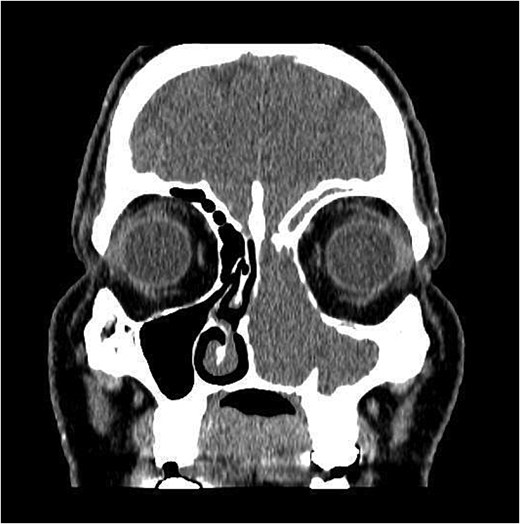

A 47-year-old male was referred to the otolaryngology clinic with history of left nasal block, rhinorrhea and suspected vestibulitis of 1 month duration. It did not improve with intranasal steroids. Upon nasal flexible scope examination, there was a left sided fleshy mass markedly affecting the airway. Computed tomography (CT) of the paranasal sinuses with contrast was requested.

CT showed a heterogeneously enhancing mass completely occluding the left nasal cavity, left ethmoidal, maxillary and frontal sinuses, extending to left pterygopalatine fossa. It is associated with bony erosion of the posterior nasal septum and the left medial maxillary wall (Figs 1 and 2). Findings were suggestive of inverted papilloma vs sinonasal malignancy. Therefore, biopsy was recommended.

Coronal section of CT paranasal sinus with contrast soft tissue window showing the mass occupying the left nasal cavity and extending to maxillary and ethmoidal sinus.